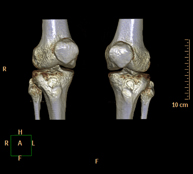

- TC Rodillas

Exploración radiológica que mediante un sistema de rayos X y detectores que giran alrededor del paciente, reconstruyendo las imágenes por ordenador (TC Multidetector), permite el estudio de huesos, músculos y articulaciones de la rodilla.